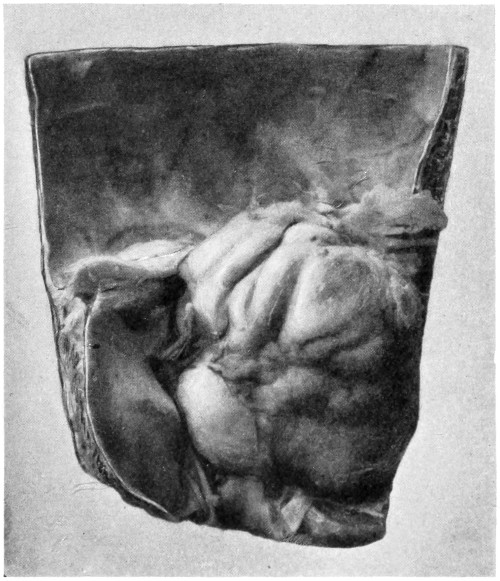

| 86. A case of Hernia cerebri and the abscess after removal | 292 |

| 77. A cerebellar abscess | 259 |